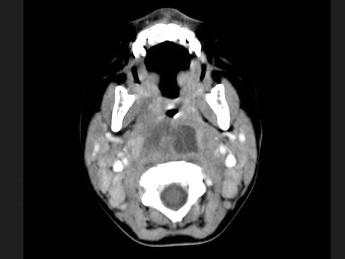

18.10個(gè)月大的嬰兒,發(fā)熱,曾患中耳炎,CT掃描如圖所示,請(qǐng)選擇正確的描述或診斷  (    )

正確答案:ABCD